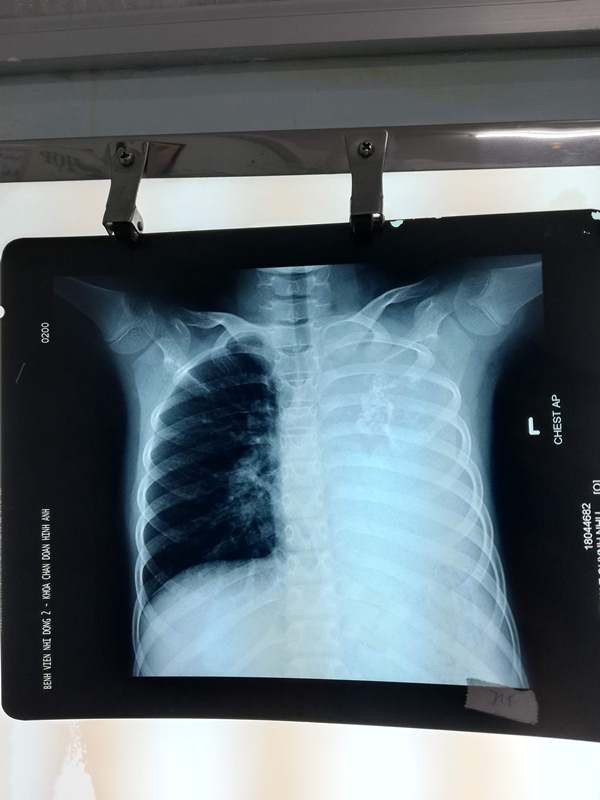

Theo các BS, bệnh nhi được người nhà đưa đến BV Nhi Đồng 2 khám do tình trạng ho kéo dài, khó thở khi gắng sức. Qua hình ảnh CT scan ngực, các BS đã phát hiện một khối u phổi khổng lồ xâm lấn toàn bộ phổi trái gây tắc đồng thời phế quản gốc trái và động mạch phổi trái khiến bệnh nhi chỉ hô hấp bằng 1 phổi bên phải.

Cứu sống bé gái suýt chết vì bệnh hiếm thế giới chỉ 20 người mắc ảnh 1Hình ảnh khối u trên phim X-QUang